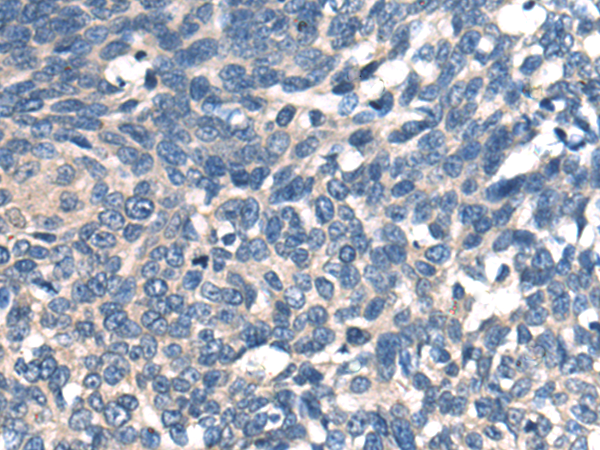

分类: 科研抗体货号: P13824别名: CMS10; CMS1B; FADS3; C4orf25应用: IHC反应种属: Human, Mouse